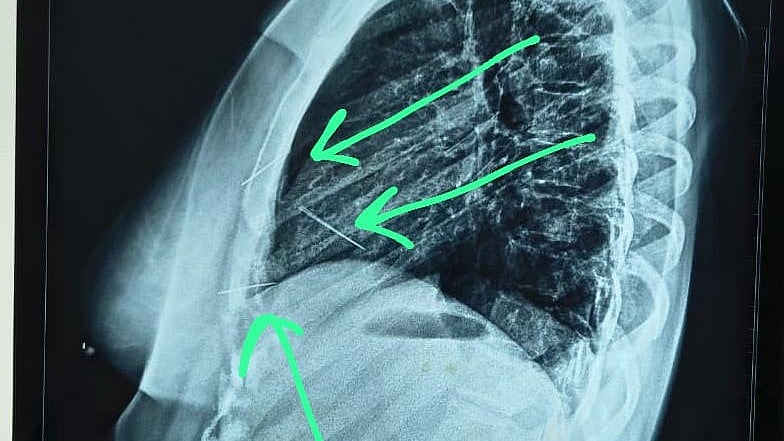

Further imaging revealed that three needles were deeply embedded in the chest one reaching dangerously close to the heart while another sharp, rusted metal fragment was lodged inside her skull.

A synchronised surgical and anaesthetic team, led by eminent Cardiothoracic & Vascular Surgeon Dr Sami Anwar Khan, successfully removed the chest-embedded needles, while general surgeon Dr Abhishek Kansal extracted the metallic fragment from the head. Surgical reports revealed a sharp object lodged in the pectoral muscle, another penetrating the pericardium, and a third fixed near the left ventricle wall. The skull object, rusted and pointed, indicated prolonged presence.